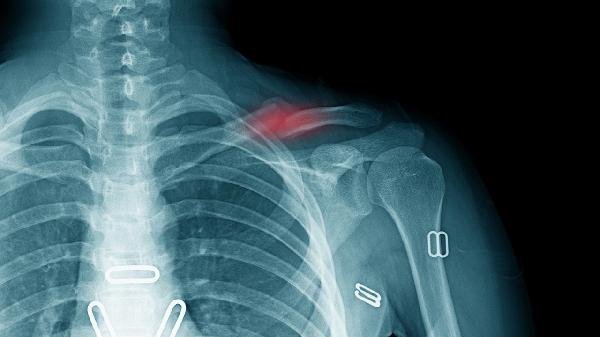

锁骨骨折保守治疗后一般需要4-6周开始逐步锻炼,具体时间取决于骨折愈合情况、年龄、康复计划、营养状态和并发症等因素。

骨折线模糊是开始锻炼的基础指标,需通过X光确认骨痂形成。临床愈合通常需3-4周,此时可进行被动关节活动。完全负重训练需等待骨性愈合,约需8-12周。

儿童患者因骨膜较厚、血供丰富,2-3周即可开始轻柔活动。中青年患者需4周以上,老年患者因骨质疏松可能延长至6-8周,需配合钙剂补充。

第一阶段0-2周进行手指腕部活动,第二阶段2-4周增加肘关节屈伸,第三阶段4周后逐步开展肩关节钟摆运动。物理治疗师会根据肌力测试制定个性化方案。

合并臂丛神经损伤需延迟至6周后锻炼。出现反射性交感神经营养不良时,应优先进行疼痛管理。二次移位风险高的粉碎性骨折需延长固定时间2-3周。

康复期建议采用高蛋白饮食搭配奶制品,每日补充500mg钙剂及800IU维生素D。初期避免提拉超过2kg重物,6周内禁止对抗性运动。睡眠时保持30°半卧位减轻疼痛,使用三角巾固定期间每小时活动手指预防僵硬。水中浮力训练可减少关节负荷,推荐骨折4周后开始每周2-3次泳池康复。定期复查X光片,若出现异常疼痛或骨擦感应立即中止锻炼。